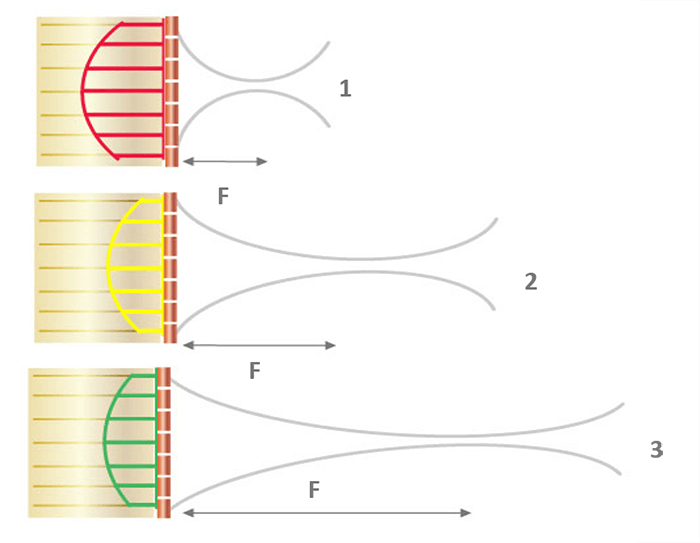

The beam width can be further reduced by adjusting the focal area. It is, therefore, useful to position the target structure in the focal zone to obtain the best possible lateral resolution. The beam diverges increasing its width while propagating in depth. It is possible to focus the ultrasound beam to obtain a narrow beam at the focal length, and thus improve the lateral resolution. Focusing can be accomplished either mechanically, or electronically via a multi-element array.

Electronic Beam Focusing

The focusing of some transducers can be adjusted to a specific depth for each transmitted pulse. The transducer is made up of an array of several piezoelectric elements, rather than a single element compared to the fixed focus transducer. As shown in this animation, the elements are arranged in either a straight, or curved line in the linear array.

Focusing is achieved by not applying the electrical pulses to all of the transducer elements simultaneously. The pulse to each element is passed through an electronic delay The outermost elements will be pulsed first, which produces ultrasound that begins to move away from the transducer. The other elements are then pulsed in sequence, working toward the center of the array.

The centermost element will receive the last pulse. The pulses from the individual elements combine in a constructive manner, to create a curved composite pulse, which will converge on a focal point at some specific distance or depth from the transducer.

The focal depth is determined by the time delay between the electrical pulses. Focal Pulses can be changed electronically to give a good image detail at various depths within the body, rather than just one depth compared to the fixed focus transducer. One approach is to create an image by using a sequence of pulses, each one focused on a different depth or zone within the body.

Another approach is a group of piezoelectric elements that work together to produce the focused beam. Each of the transducers is excited with time offsets. The combination of several focal lengths on transmission improves the quality of the image. In return, the frame rate is decreased by a factor equal to the number of selected focal lengths. And last, the image is reconstructed by zone.